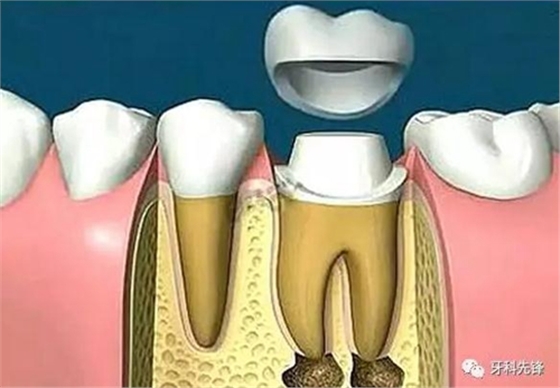

當牙齒做完根管治療,由于牙齒自身的結構及治療的需要,牙冠中心一般都是空的,這時,如果直接做牙套,其抗折斷力很差,一般都需要在牙根上打上樁釘,做出個結實的核,以對抗牙齒使用中的折斷力。

對于后牙來說,做完根管治療之后一定要做上牙冠,否則在承受咬合力量時,牙齒容易出現斷裂。少數做完根管治療的后牙,若是要做單一的牙冠,只需將所剩牙質修補足夠,則可不需做樁釘,但若做完根管治療的后牙是要作為假牙的基牙,則無論牙質所剩多少,最后都能做好樁釘。

現在非常普遍的烤瓷牙冠外形逼真,不變色,使用時間長,能夠更好的保留經過根管治療后的牙齒??敬裳拦诨痉謨煞N:一種是金屬的,一種是全瓷的。

因為牙齒沒有了神經,就失去了活力,沒有了營養(yǎng)的供給,牙體會逐漸變黑,影響美觀。而全瓷牙的色澤無論在燈光下和自然光下都能保持自然色,因此備受影視明星和公眾人物的追捧。全瓷冠具有良好的生物相容性,不會給口腔環(huán)境帶來影響,可以在口腔內永久保存。因其材料是由全瓷材料組成,放置在口腔內,牙齦周圍不會有難看的黑線出現,美觀效果極佳。

相對來說,金屬烤瓷牙的效果會有點不盡如人意。因為如果做的時間長了,金屬就容易被氧化,被氧化后的金屬離子游離出來,就會使牙齦邊緣出現黑線。況且有些金屬會刺激牙齦,對人體是有害的。所以,不管是從美觀角度還是健康立場來說,醫(yī)生都建議大家選用全瓷的烤瓷牙來保護根管治療后‘脆弱’的牙齒。